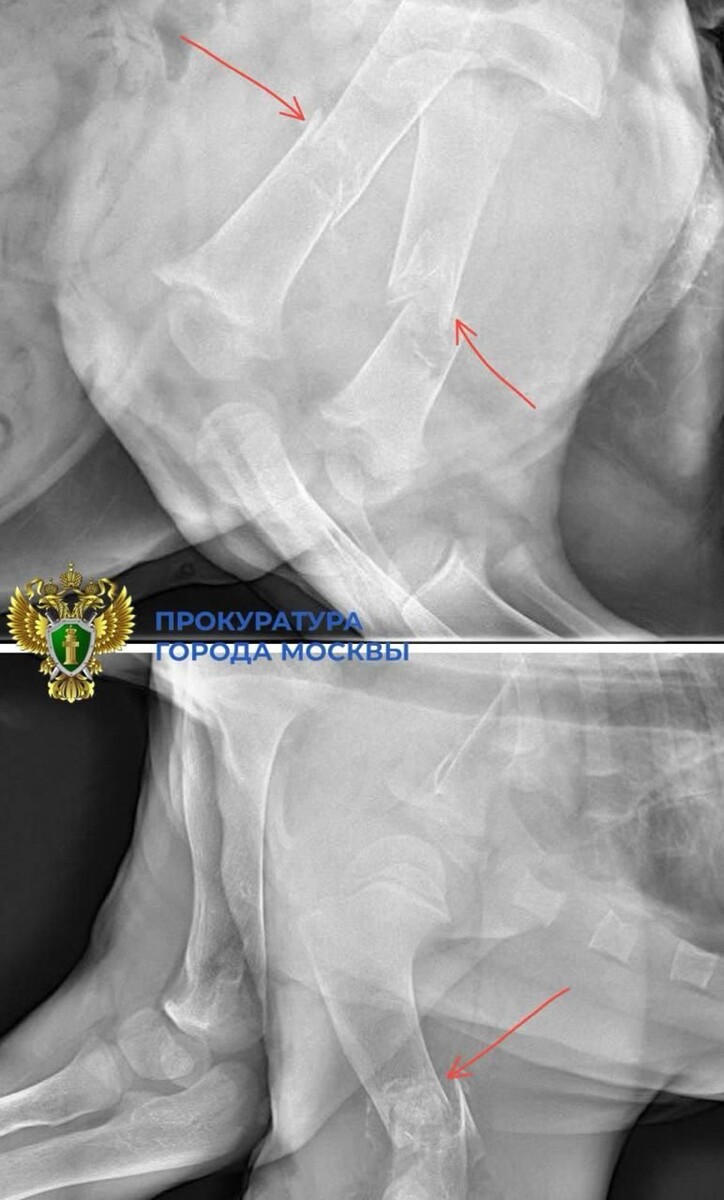

Первичный ветеринарный осмотр выявил у нее многочисленные травмы: переломы трех конечностей и повреждение позвоночника. Также у львицы было общее истощение костной ткани, вероятно, из-за плохих условий содержания и питания.

«Только что привезли маленькую львицу. Ей очень больно и плохо. Перелом позвоночника, перелом обеих бедренных костей, перелом плеча и сломан хвост. Прогнозы пока очень осторожные. К сожалению, услышали то, чего больше всего боялись. И сразу сообщаем Вам», — писали волонтеры в Telegram-канале.